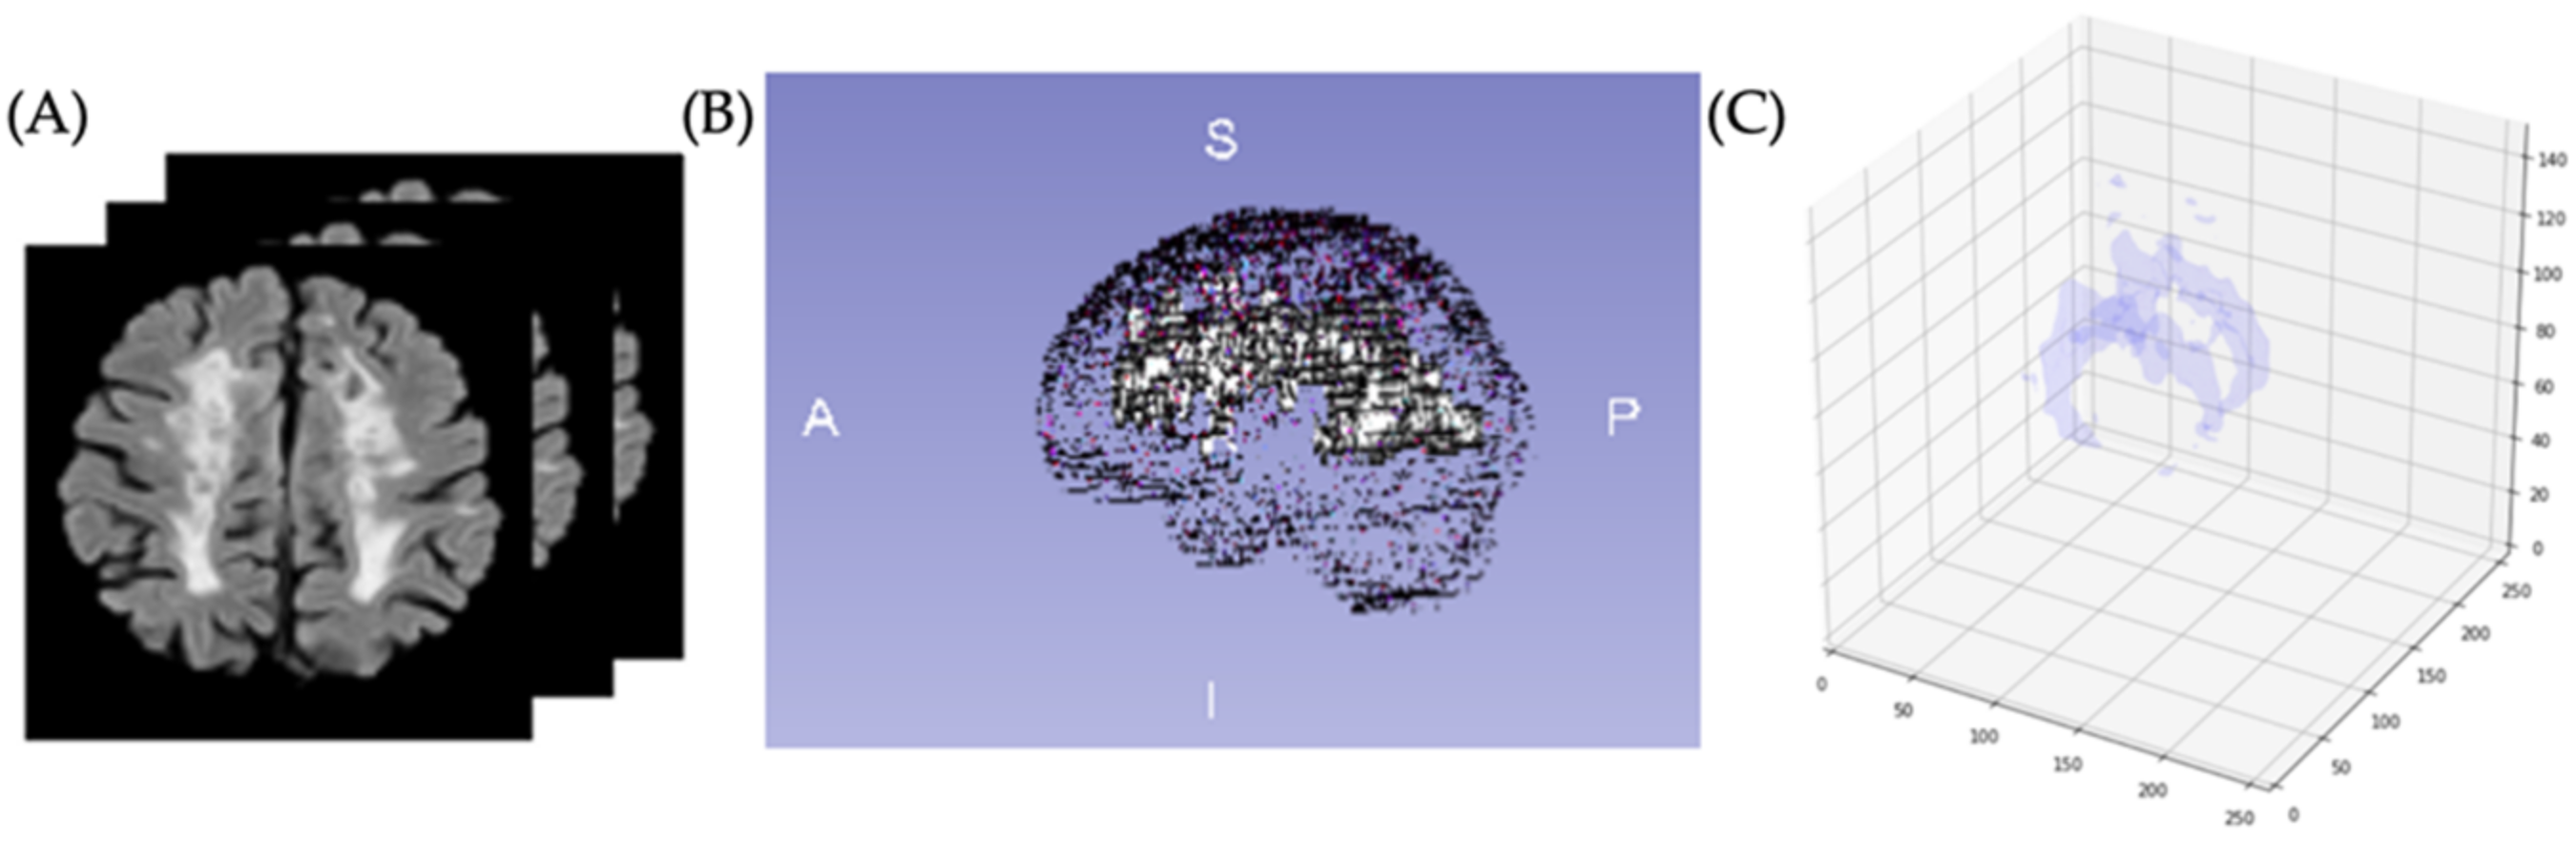

Finally, to improve the signal intensity variability in MRIs caused by magnetic field inhomogeneities, we applied the image bias correction filter (N4ITK) in step six of the preprocessing after automatic brain extraction. Figure 6 illustrated an example of a slice with the application of the bias correction step. The brain extraction process and bias correction were applied to all the slices in the exam (each patient), and we were able to see the volumetric representation of the extracted brain (see Figure 7).

Figure 6.

(A) Rigidly registered image. (B) Skull-stripped image. (C) Bias correction filter. (D) Final image.

Figure 7.

Brain volume after the brain extraction process applied to all slices for one patient.